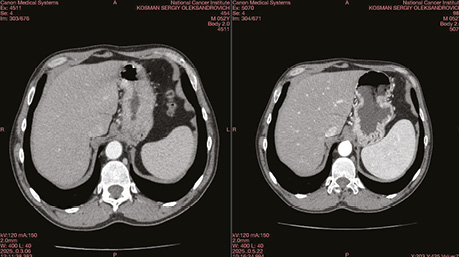

Передопераційну хімієтерапію хворий переніс задовільно. Ефект хімієтерапії — частковий регрес (стоншення стінок на 41%) (рис. 3).

Рис. 3. Радіологічний ефект після проведення 4 курсів неоад’ювантної хімієтерапії